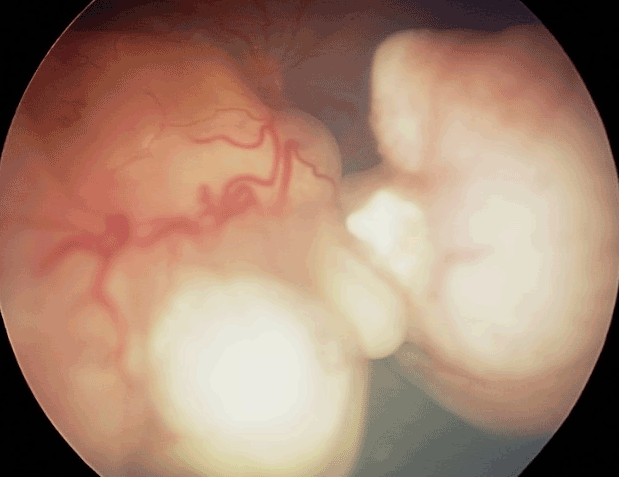

Mélanome choroïdien Diagnostic du mélanome choroïdien Il s'agit de la tumeur intraoculaire primitive la plus fréquente de l'adulte. Le mélanome uvéal peut toucher la choroïde (site le plus fréquent que nous décrirons ici), le corps ciliaire ou l'iris. Son incidence annuelle est d'environ 500-600 nouveaux cas par an en France. L'âge médian au diagnostic est de 62 ans mais il peut survenir à tout âge. Il touche généralement les sujets caucasiens, avec un surrisque parmi les personnes ayant les yeux bleus, pour des raisons non encore élucidées. Le diagnostic est clinique, ce qui est une singularité en oncologie, car l'obtention d'une preuve histologique par biopsie invasive exposerait à un risque de dissémination orbitaire. Il repose sur l'examen du fond d'œil et l'échographie oculaire. On observe une lésion choroïdienne en relief (Figures 1 et 2), de morphologie en dôme ou en champignon (Figure 3). La lésion est souvent pigmentée mais peut également être achrome (Figures 4 et 5), ce qui doit alors faire suspecter une métastase choroïdienne, avec réalisation d'un bilan d'extension complet, à la recherche d'une néoplasie primaire ayant métastasé à l'œil. Un décollement de rétine exsudatif peut être présent (Figure 6). Une hémorragie intravitréenne peut s'associer et masquer la tumeur. Ces deux présentations impliquent de devoir réaliser systématiquement une échographie oculaire en cas de décollement de rétine exsudatif sans déhiscence retrouvée, ou en cas d'hémorragie intravitréenne. En effet, une éventuelle chirurgie intraoculaire par vitrectomie sur un mélanome uvéal méconnu peut entraîner une dissémination tumorale.

Figure 2 Mélanome choroïdien inférieur.